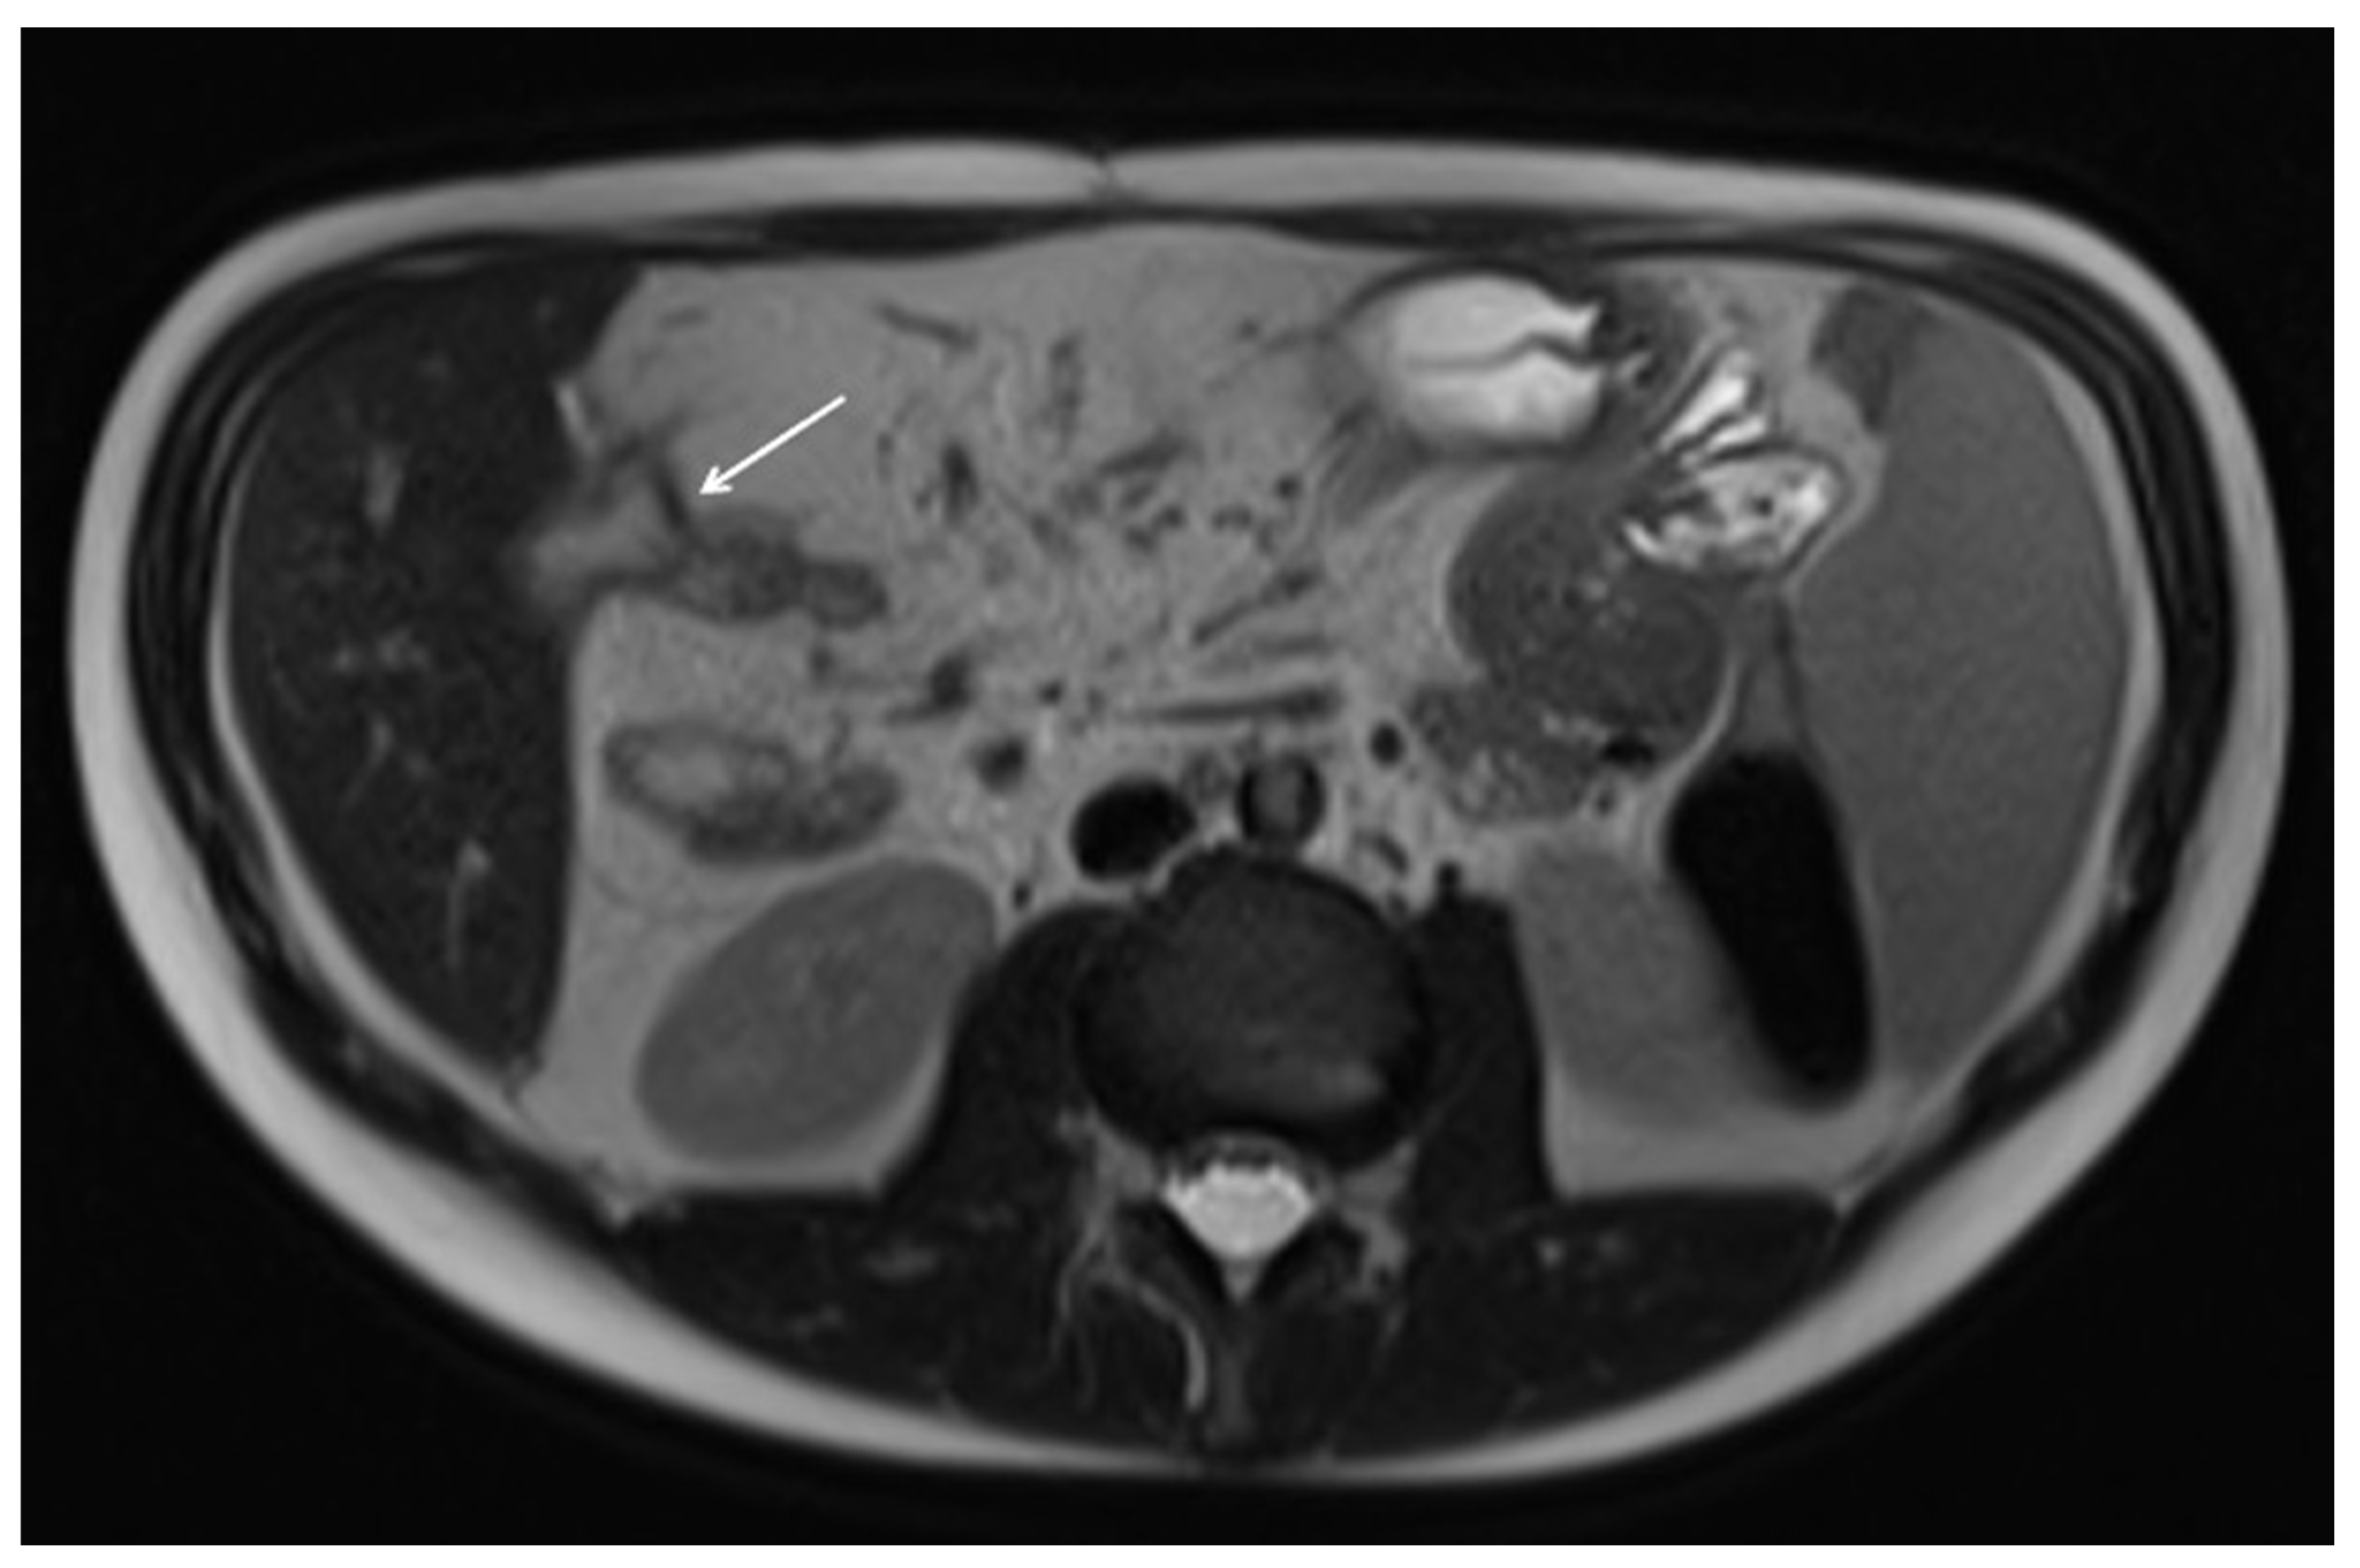

10. Imaging Findings Associated with Active CD Inflammation

| Imaging Findings Associated with Active CD Inflammation |

Segmental mural hyperenhancement

Wall thickening

| Intramural edema |

| Perienteric edema and/or inflammation |

| Engorged vasa recta |

| Fibrofatty proliferation |

| Lymphadenopathy |

| Restricted diffusion |

| Diminished motility |